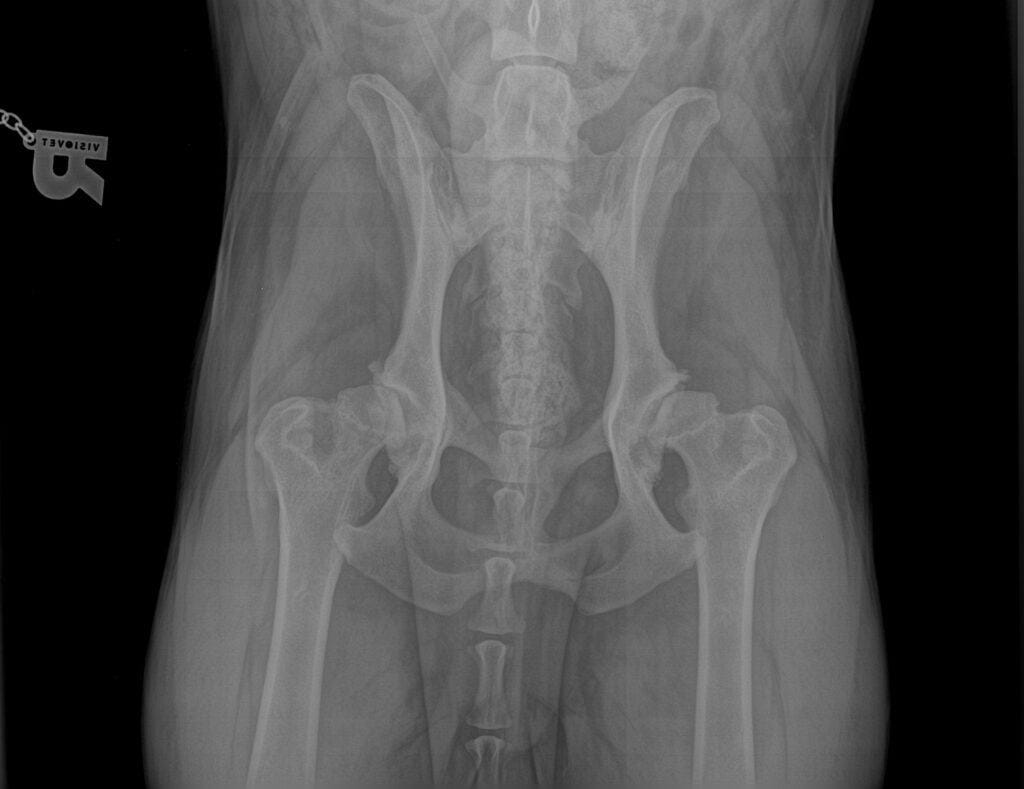

A csípő izületi diszplázia (dysplázia) általában nagytestű kutyákat érint, de szenvedhetnek tőle kisebb testűek, sőt macskák is. Ez a veleszületett rendellenesség, sokszor évekig rejtve marad, és csak közép-idős korban okoznak problémát, amikor már erősen gyulladtá és kopottá válik az izület. Mindenképp ajánljuk a nagytestű kutyák (25 kg-nál nagyobbak), vagy klinikai tünetet mutató állatok szűrését, mert az idejében észrevett diszplázia megfelelő életmódváltoztatással, fizikoterápiával, izületvédőkkel jól karban tartható. Így az állat tünetmentesen élhet elkerülve a fájdalom miatti hosszas gyógyszerszedést, vagy akár a műtétet.

Súlyos csípődiszplázia (bal) : a combcsont fejek nem illeszkednek a medence csonthoz. A rossz terhelés miatt idült gyulladás jelei láthatóak mindkét izületben. Egy egészséges csípő (jobb) oldal.